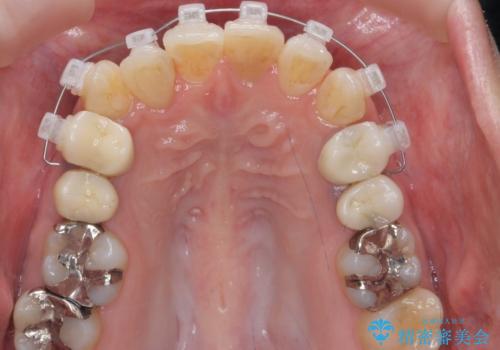

右上2番をしっかり並べるにはワイヤー矯正を上顎部分的に用いて、最後全体マウスピース治療を行いました。

上顎前歯は神経がない歯で色も変わってきていたためセラミックでかぶせています。